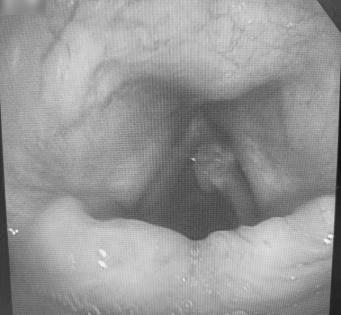

在充分评估支气管镜检查风险后,医生在局麻下为老者实施了电子支气管镜检查:右侧声带前中 1/3 可见肿瘤组织致喉狭窄。术后行活检组织病理证实为「高分化鳞癌」。